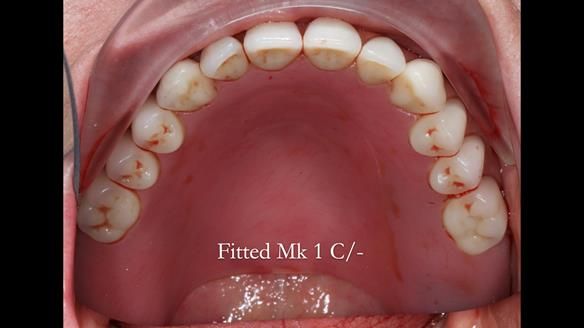

This newsletter describes the full protocol workflow of a complete upper denture and a lower partial denture for Jo.

The clinical situation and treatment process is shown in detail below. I provided the clinical work. Rowan Garstang provided the technical work. This treatment took 25 visits over a period of 12 months.